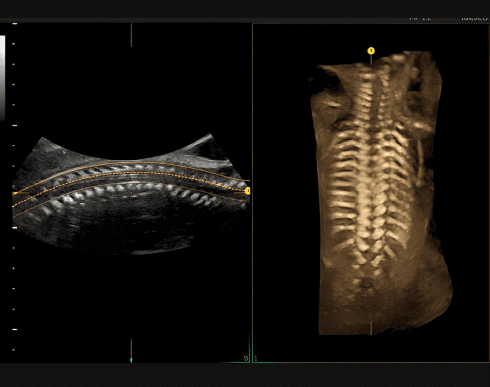

Spine Trace

Просо та легко отримуйте складні 3D зрізи. Просто намалюйте хребет, і система автоматично створить коронарний зріз.